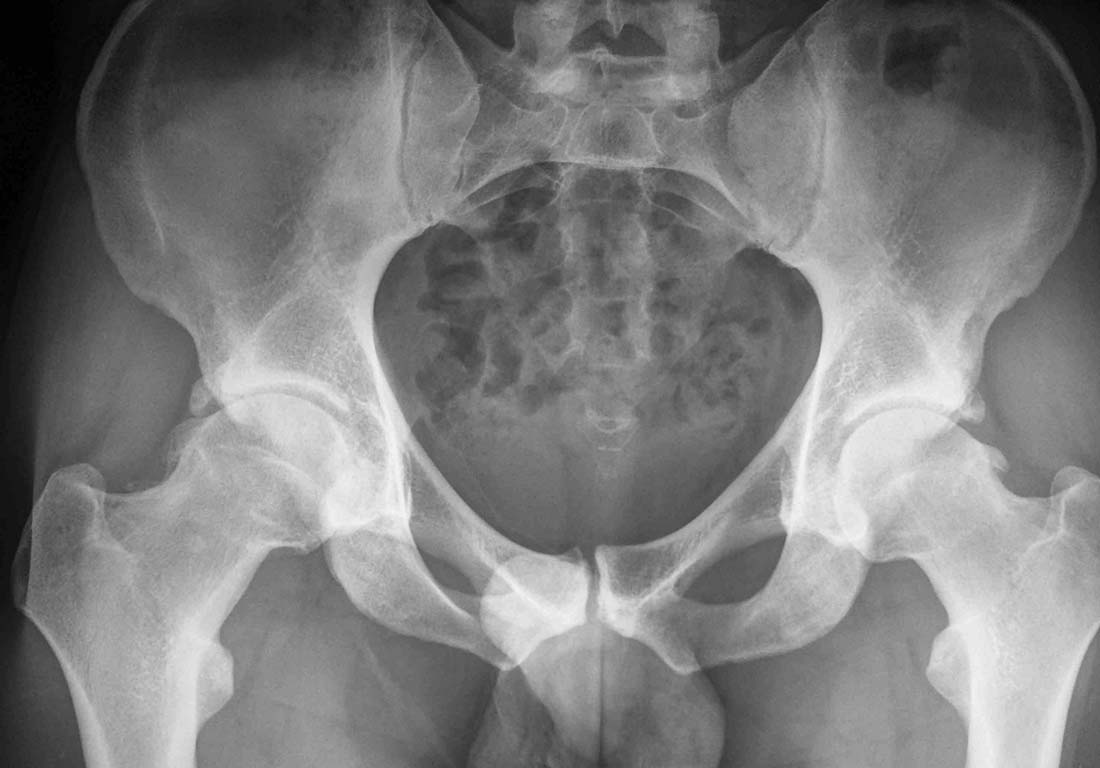

Обратился на консультацию молодой человек с жалобами на дискомфорт в правом тазобедренном суставе.

объективно, имеется ограничение движений в правом т/б суставе, болевой синдром минимальный. не курит, спортсмен. Вопросы:1. лечит ли у нас кто-нибудь эти проблемы артроскопически, возможно ли это в данном случае.Если да, то как можно отправить пациента. если платно -то сколько стоит?2. Тема уже обсуждалась на форуме, у меня найти не получилось, может кто-нибудь скинет ссылку.Заранее спасибо.

Привет, Макс. Чтобы уточнить объем вмешательства нужно дополнительные укладки и возможно КТ. Если для ликвидации ФАИ достаточно удалить наросты в области верхних и передних отделов шейки,то артроскопически это возможно.

мне кажется недостаточно, тут вроде смешанный тип